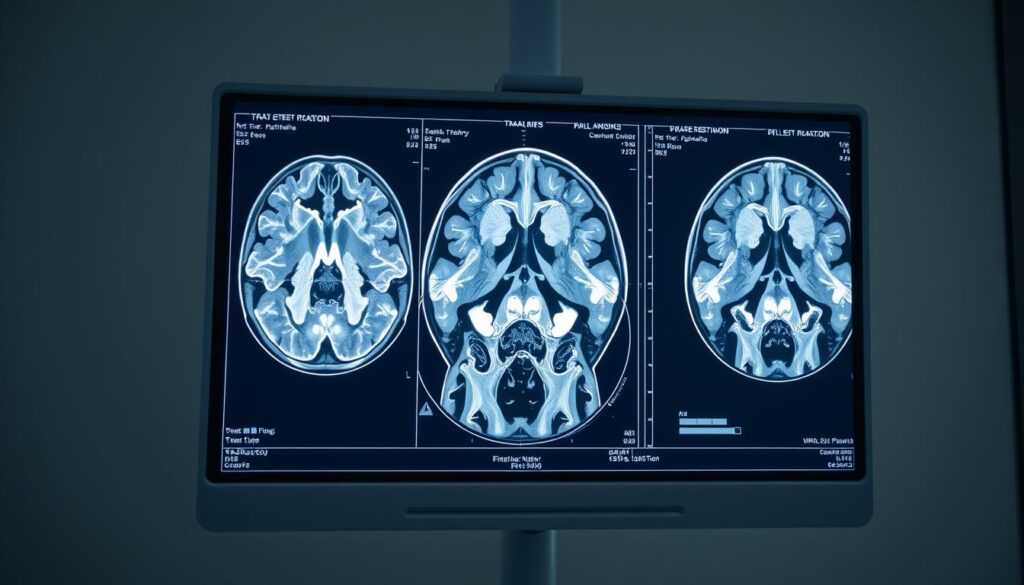

La resonancia magnética es un método diagnóstico moderno que nos permite obtener imágenes detalladas del interior del cuerpo humano sin usar radiación. Este examen se basa en principios de funcionamiento resonancia magnética, donde se emplea un imán potente y ondas de radio. De este modo, logramos visualizar estructuras internas con gran claridad, facilitando una evaluación precisa de diversas condiciones de salud.

El proceso comienza con el paciente siendo colocado dentro de un dispositivo de resonancia magnética, donde el imán crea un campo magnético que reorganiza temporalmente los átomos de hidrógeno en el cuerpo. Al aplicar ondas de radio, los átomos liberan energía en forma de señales que son capturadas para crear imágenes. Este funcionamiento resonancia magnética ofrece un nivel de detalle superior a otros métodos, permitiendo evaluar no solo huesos, sino también tejidos blandos, órganos y sistemas internos.

Los usos resonancia magnética son amplios y variados, siendo especialmente efectivos para identificar lesiones musculoesqueléticas, trastornos neurológicos y problemas cardiovasculares. Gracias a su capacidad para diferenciar entre diferentes tipos de tejidos, se convierte en una herramienta fundamental en el diagnóstico médico actual. En el Laboratorio Arquimedes, aplicamos esta tecnología para mejorar la calidad de los diagnósticos y contribuir a un tratamiento más efectivo de nuestros pacientes.